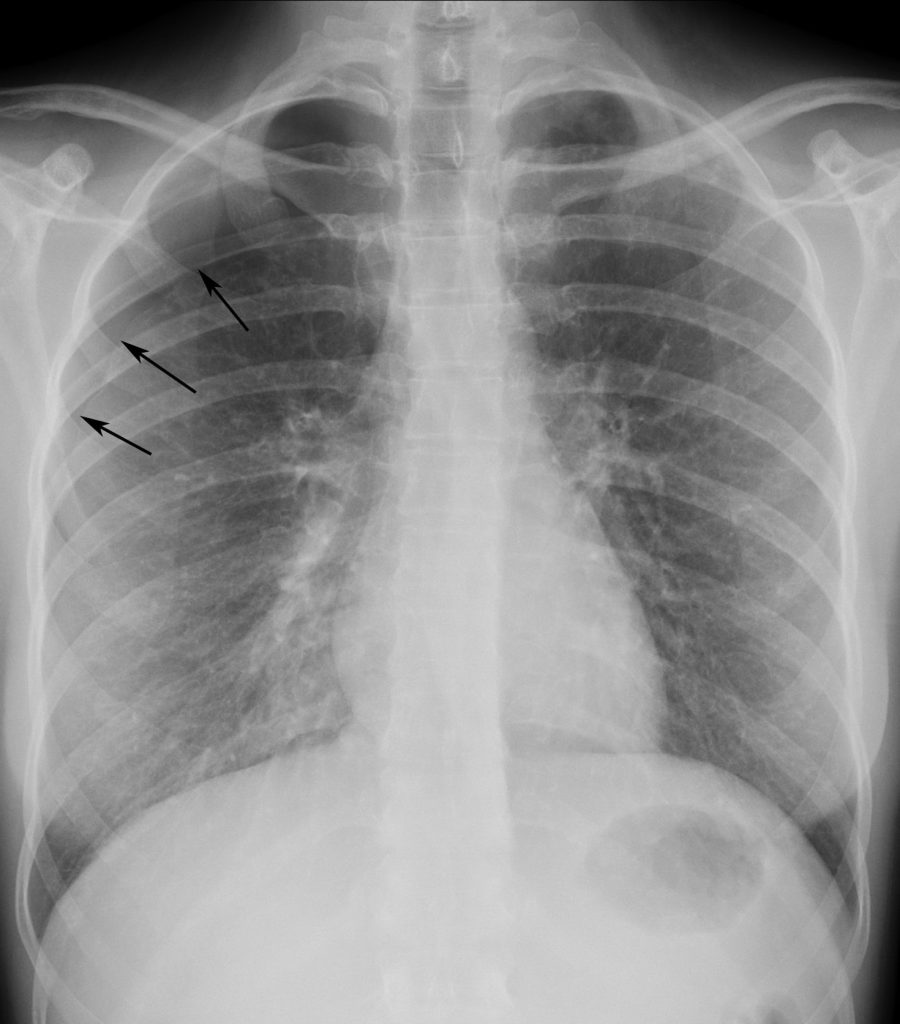

Fig. 98.2. Radiographie de face. Pneumothorax droit de faible abondance.

La ligne fine qui représente la plèvre pulmonaire (flèches) et qui croise les côtes supérieures n’est visible qu’à l’apex du poumon.

Source : CERF, CNEBMN, 2022.